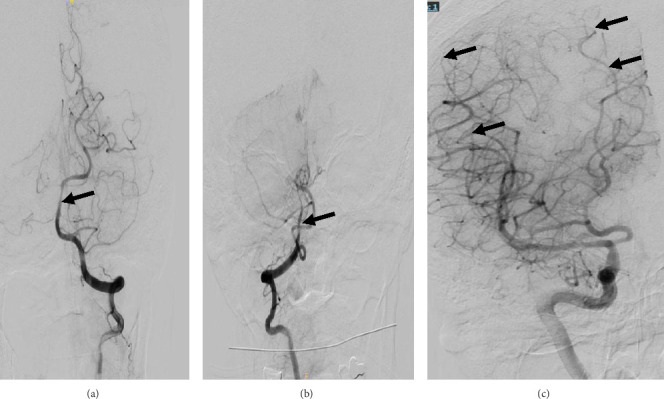

一名65岁妇女,表现为肺炎球菌败血症和脑膜炎。尽管适当的抗菌药物治疗和静脉注射地塞米松,她的精神状态没有改善。脑显像提示脑血管炎。开始大剂量静脉注射甲基强的松龙治疗后,病情迅速好转。完成3周口服泼尼松逐渐减少治疗一周后,患者的神经认知缺陷复发。更广泛的诊断评估,包括常规血管造影,再次与脑血管炎的推定诊断一致。大剂量静脉注射甲基强的松龙和较长时间的口服强的松逐渐减少导致她的疾病缓解,精神状态和左侧偏瘫有明显改善。脑血管炎是肺炎球菌性脑膜炎的一种罕见但潜在致命的并发症,可能难以识别和治疗。脑活检在诊断中的作用尚不清楚,由于其罕见性,该病的治疗缺乏确凿的循证数据。

A 65-year-old woman presented with pneumococcal sepsis and meningitis. Despite appropriate antimicrobial therapy and intravenous (IV) dexamethasone, her mental status did not improve. Findings of brain imaging were suggestive of cerebral vasculitis. Her condition improved rapidly with the initiation of high-dose IV methylprednisolone therapy. One week after completion of a 3-week oral prednisone taper, the patient's neurocognitive deficits recurred. A more extensive diagnostic evaluation, including conventional angiography, was again consistent with a presumptive diagnosis of cerebral vasculitis. High-dose IV methylprednisolone and a more prolonged taper of oral prednisone led to remission of her disease, with marked improvement in mental status and left-sided hemiparesis. Cerebral vasculitis is a rare but potentially lethal complication of pneumococcal meningitis that may be difficult to recognize and treat. The role of brain biopsy in diagnosis is unclear, and due to its rarity, management of this condition lacks conclusive evidence-based data.